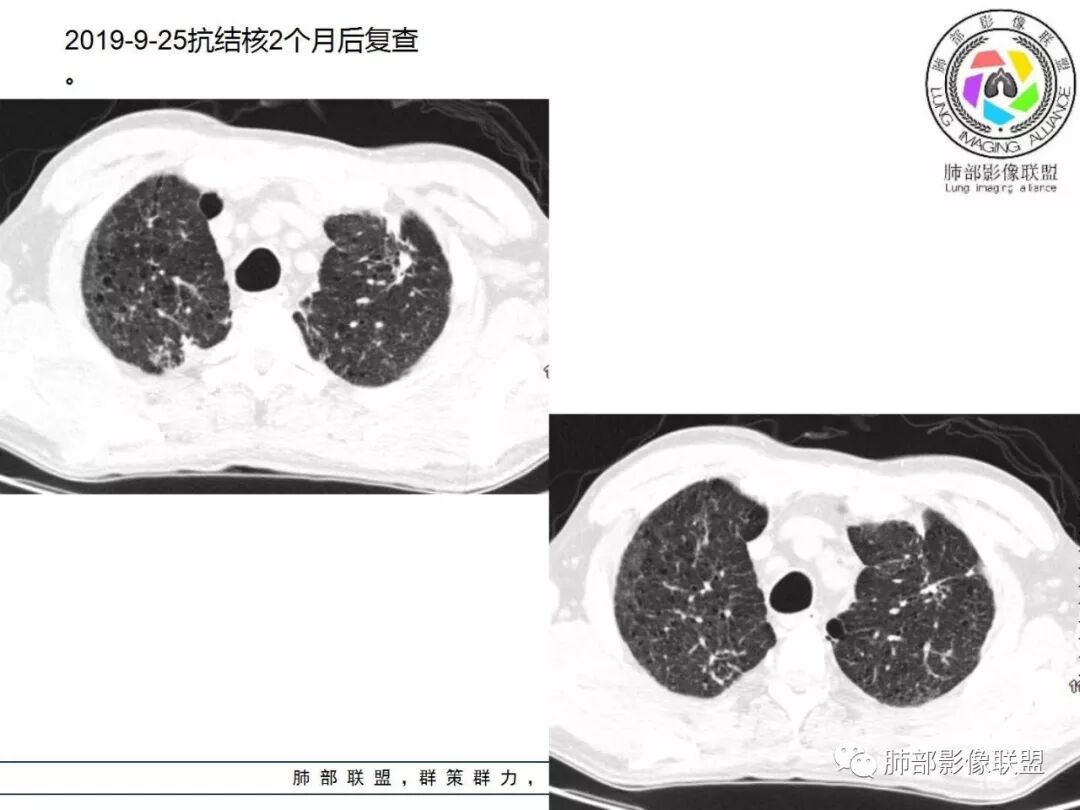

答案揭晓

间质性肺结核

病例小结

1.  老年男性,发热为主诉,体温38°-39°,发热以午后及晚上为主,伴黄痰,CRP增高,临床病史支持感染性病变;

2. 肺气肿背景(小叶中心性肺气肿);双肺多发病灶整体沿血管支气管束及胸膜下分布,以上叶及下叶背段分布为主,有实变及GGO,边界清楚,有树芽,小叶间隔及中央间质增厚,叶间裂见到多发结节,部分支气管不规则牵拉扩张,提示病灶纤维化明显,结合临床病史,考虑病灶为间质性感染,肺门及纵隔内有钙化淋巴结,小叶间隔结节,考虑淋巴道增值性疾病可能,综合常规要怀疑间质性肺结核。

3.  该病例临床提示感染,有支气管扩张,提示纤维化,需要与感染后的OP鉴别,但是OP病灶常无结节感;间质性肺结核有时与不典型结节病鉴别也比较困难,结节病常以双肺门淋巴结增大为特征。临床上结核发病率较高。